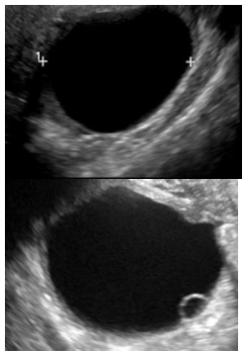

Next step?

nothing. this is a simple follicular cyst with a small peripheral follicle (cumulus oophorus)

right ovarian mass shown in the image.

most common complication?

ovarian torsion

dermoid is shown in the picture